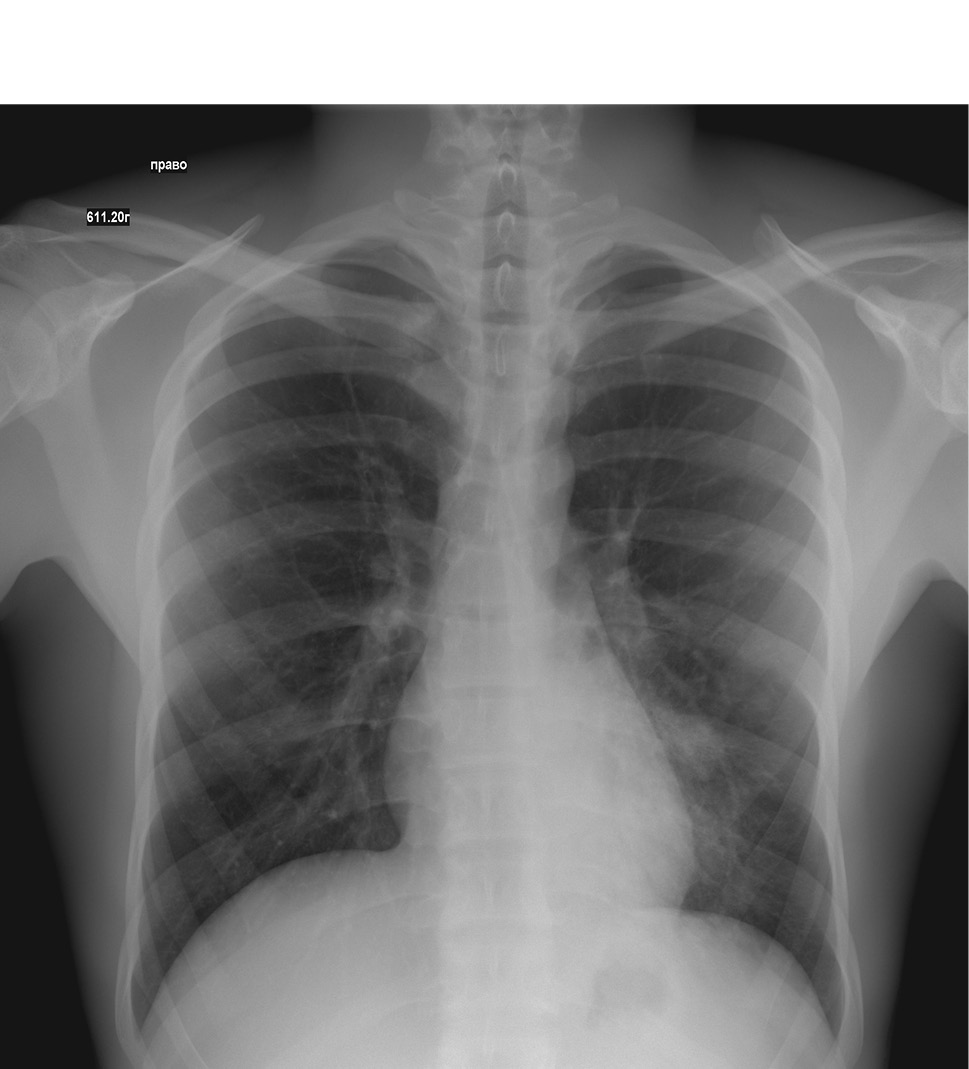

С учетом жалоб ребенка на кашель и тяжестью состояния назначено рентгенологическое исследование органов грудной клетки для исключения воспаления легких. Рентгенография 06.11.2020: форма грудной клетки цилиндрическая. Легочной рисунок с обеих сторон усилен в прикорневых зонах. На этом фоне слева, в прикорневой зоне, на уровне среднего и нижнего легочных полей отмечается снижение пневматизации из-за локального сгущения легочного рисунка за счет перибронхиальных инфильтративных изменений. Корни легких: правый — структурен, не расширен, левый — умеренно расширен, малоструктурен за счет перибронхиальных изменений. Купола диафрагмы справа и слева с четкими ровными контурами. Боковые диафрагмальные синусы свободные. Сердечно-сосудистая тень расположена срединно, в поперечнике не расширена. Аорта — без особенностей. Заключение: рентгенографические признаки левосторонней полисегментарной (S4, S5 верхней доли? в S9, S10 нижней доли?) пневмонии. Рекомендован контроль в прямой и боковой проекции через 3–5 дней лечения.

На фоне проводимой терапии у пациента в клинике сохранялись диарейный синдром, интоксикация, гипертермия. Состояние ребенка ухудшилось за счет появления признаков дыхательной недостаточности (затруднения дыхания, одышки, падения сатурации). В динамике выполнена контрольная рентгенография органов грудной клетки 09.11.2020: по сравнению с предыдущей обзорной рентгенограммой № 5189 от 06.11.2020 — отрицательная динамика в виде появления новых очагов слева и справа; двусторонняя очагово-сливная пневмония: справа — S4, S5 средней доли и S8, S9 нижней доли, слева — S4, S5 верхней доли S8, S9, S10 нижней доли (рис. 1, 2, 3).

Рисунок 1. Рентгенологическое исследование легких в прямой проекции

Рисунок 2. Рентгенологическое исследование легких в правой боковой проекции

Рисунок 3. Рентгенологическое исследование легких в левой боковой проекции

На рентгенограмме органов грудной клетки в динамике от 16.11.2020 отмечена положительная динамика с признаками уменьшения инфильтрации легочной ткани.